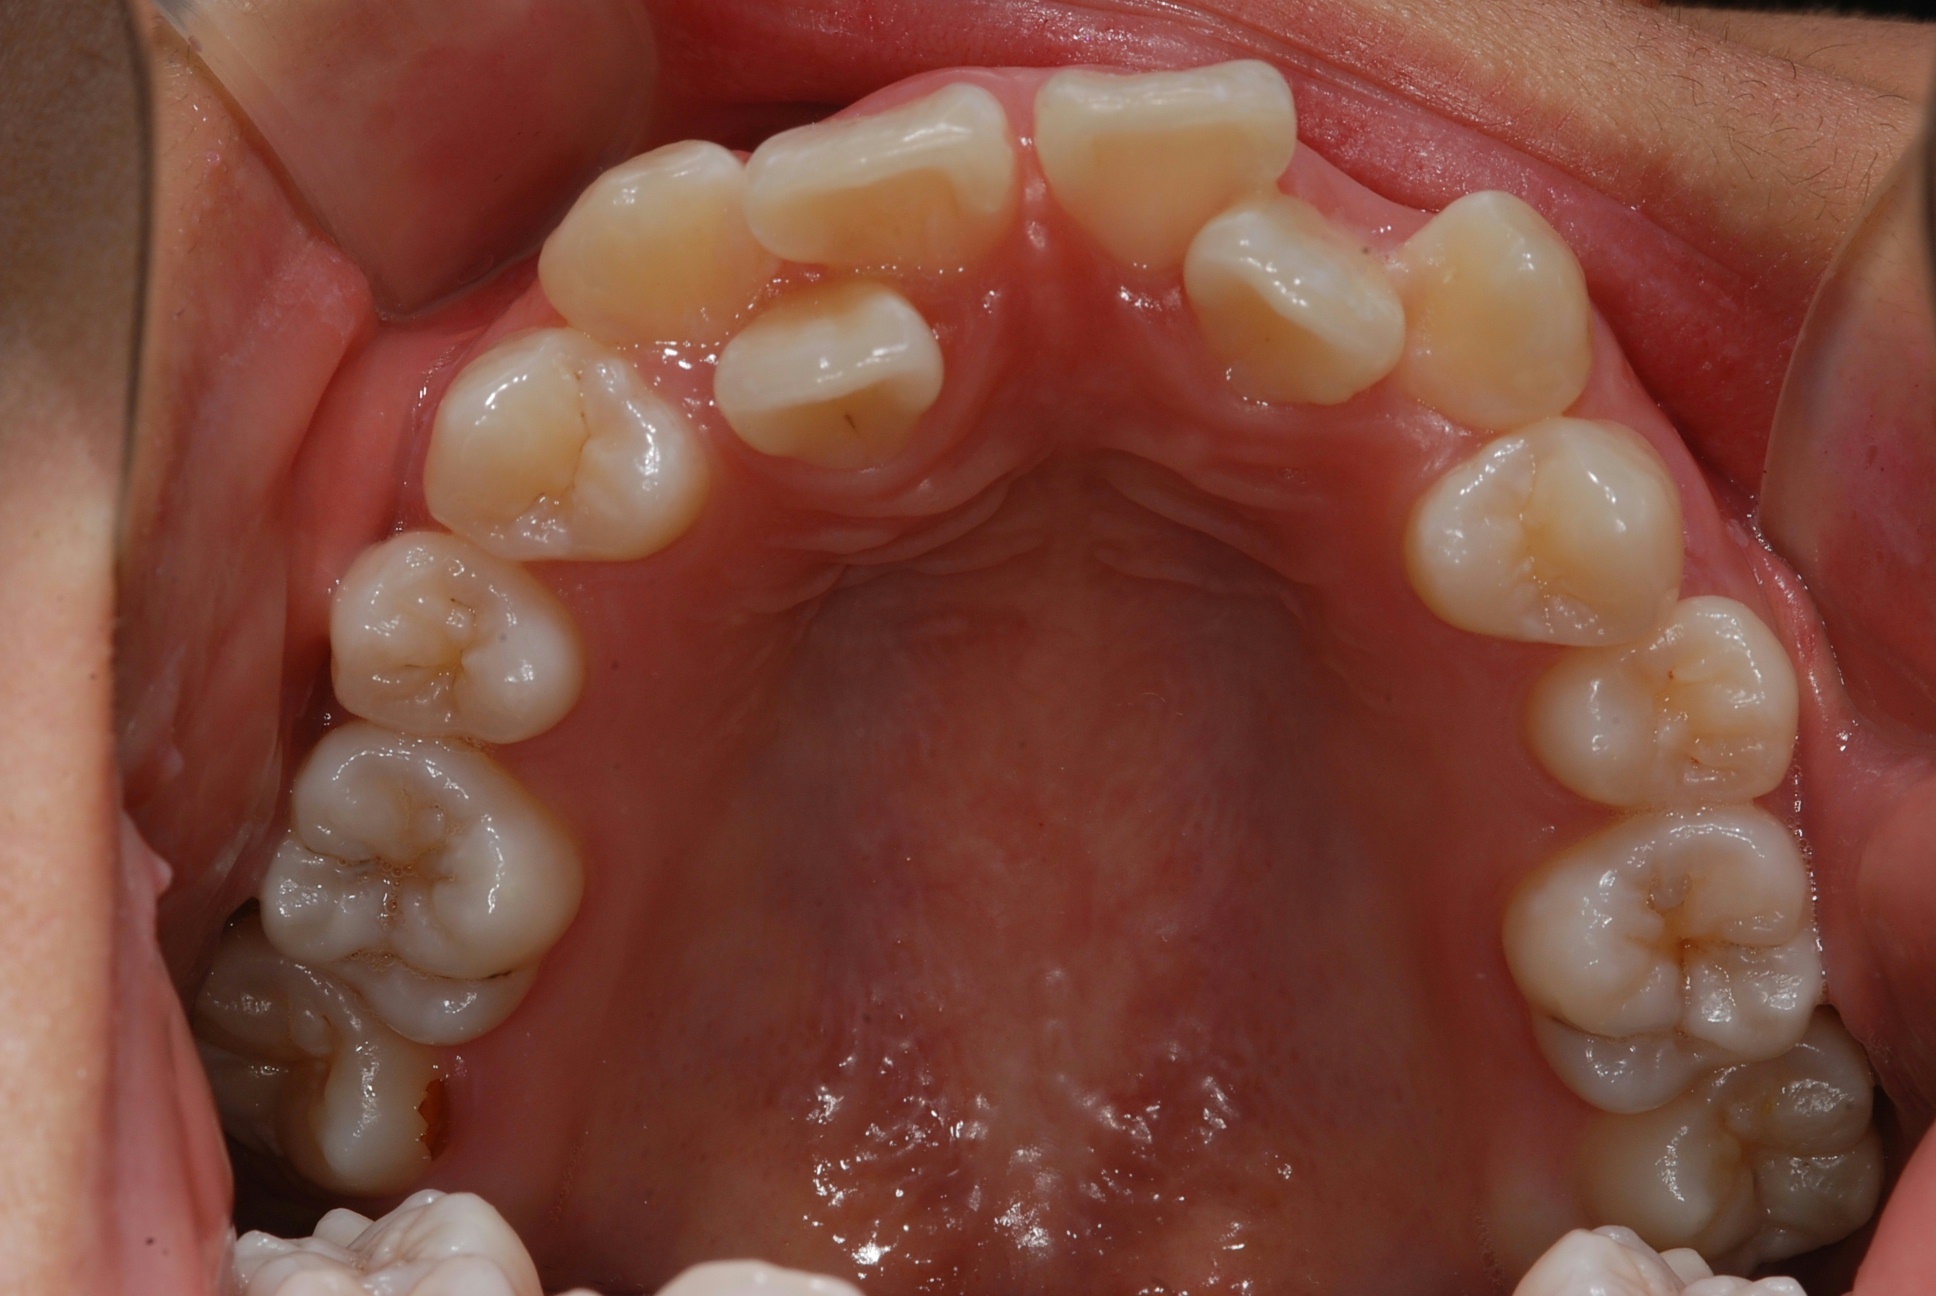

치료 전 사진입니다.